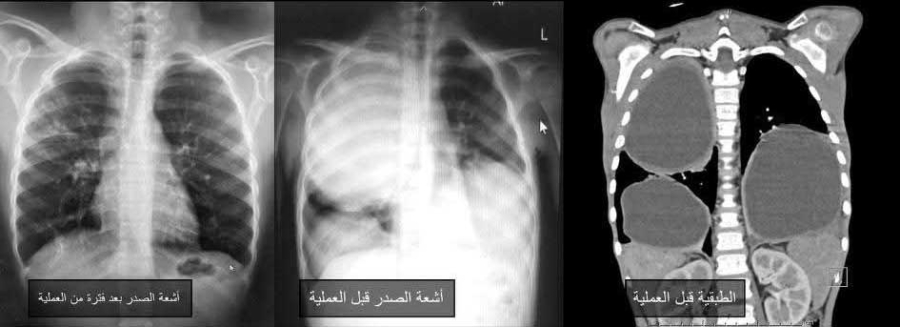

القبة نيوز - تمكن فريق جراحة الأطفال في مستشفى الجامعة الأردنية من علاج حالة نادرة لطفل يبلغ من العمر 9 سنوات، كان يعاني من "أكياس كلابية" ضخمة في كلتا الرئتين، عبر تدخلات جراحية دقيقة باستخدام المنظار الصدري، في إنجاز طبي يعد من الحالات القليلة المسجلة.

وأفاد بيان المستشفى الصادر اليوم الأحد، أن ندرة الحالة تكمن في أن "الأكياس الكلابية" عادة تصيب الكبد، وقد تنتقل لاحقاً إلى الرئتين، بينما إصابة الرئتين فقط وبشكل متعدد وضخم في الجهتين تعد من الحالات النادرة جداً. وقد اكتشف الحالة استشاري أمراض التنفسية والصدرية لدى الأطفال، الدكتورة إيناس الزيادنة، وفريقها الطبي، دون أن تظهر أعراض واضحة على الطفل.

وساهم استخدام المنظار والثقوب الجراحية الصغيرة في تسريع تعافي الطفل بعد العملية الأولى للرئة اليمنى، ما أتاح إجراء العملية الثانية للرئة اليسرى بعد نحو أسبوعين، بنفس التقنية. وقد تعافى الطفل تماماً وغادر المستشفى خلال مدة قياسية، مع متابعة طبية مستمرة أكدت عودته لممارسة حياته الطبيعية دون أي مضاعفات.